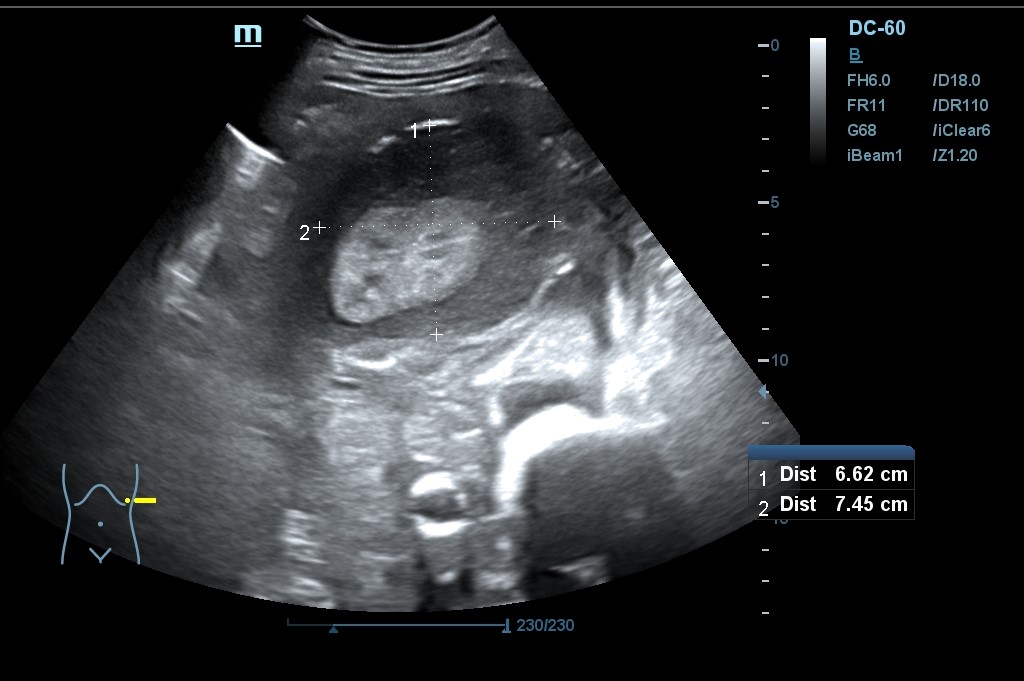

Hallazgo de lo que impresiona de nefromegalia izquierda de aproximadamente 14 cm con hidronefrosis bilateral grado 2.

Tras la segunda ecografía se deriva a la paciente a la Unidad de Diagnóstico Rápido de Medicina Interna donde ingresa para completar estudio. Tras ecografía en la que informan de extenso tejido hipoecoico periaórtico y perirrenal izq. (nefromegalia izq.) con extensión nodular al mesenterio, se establece la sospecha de síndrome linfoproliferativo, así como en un TC posterior y que se confirma como Linfoma No Hodgkin mediante biopsia.